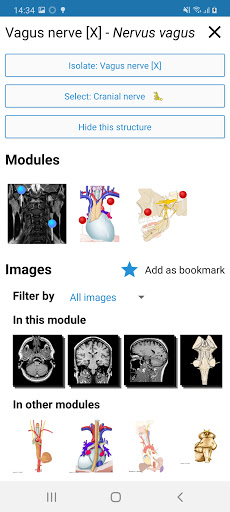

- Ketuk label untuk menampilkan struktur anatomi

*Peningkatan tampilan detail bagian anatomi untuk memudahkan identifikasi dalam gambar modul saat ini dan modul lainnya.

-Dalam tampilan detail struktur anatomi , pin sekarang menunjukkan struktur terkait di semua gambar yang ada

- "Filter oleh", dalam tampilan detail Anda sekarang dapat menyaring gambar yang mengandung struktur anatomi oleh modalitas